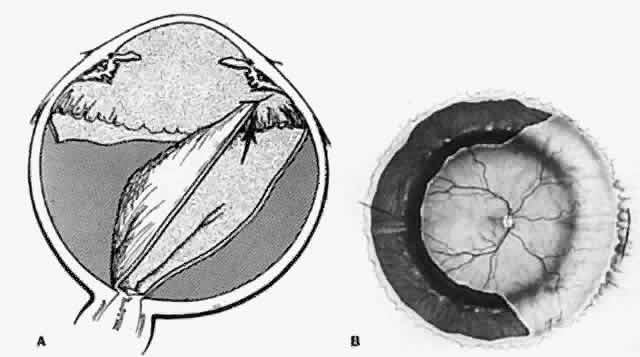

and perfluorocarbon liquids. Late Retinal Breaks Caused by Contracting Bands and Membranes Retinal detachments caused by contracting membranes are characteristic

of penetrating injuries.20 Shrinking transvitreal membranes initially cause traction detachments

of the retina opposite the site of scleral perforation (Fig. 6). In approximately 40% of cases, continued traction causes a dialysis

at the vitreous base and consequent rhegmatogenous retinal detachment (Fig. 7).20 Retinal incarceration in a scleral perforation produces a less common

but equally characteristic traction retinal detachment (Fig. 8). Retinal folds radiate from the site of incarceration. Associated vitreous

prolapse and entrapment cause traction on the adjacent vitreous

base with consequent detachment of the underlying peripheral retina and

pars plana epithelium. A retinal fold is created at the posterior border

of the vitreous base, which becomes increasingly prominent because

of the contracture of membranes interposed between the vitreous base

and the incarceration site. Progressive traction by this membrane may

cause breaks in the folded retina and consequent rhegmatogenous detachment (Fig. 9).  Fig. 6. Transvitreal traction causes tractional retinal detachment (A) opposite

perforation site (B). (Michels RG, Wilkinson CP, Rice TA: Vitreous Surgery. Retinal Detachment, p 210. St. Louis, CV

Mosby, 1990) Fig. 6. Transvitreal traction causes tractional retinal detachment (A) opposite

perforation site (B). (Michels RG, Wilkinson CP, Rice TA: Vitreous Surgery. Retinal Detachment, p 210. St. Louis, CV

Mosby, 1990)

Fig. 7. Retinal dialysis caused by traction of shrinking membrane. Location of

scleral laceration (A). Vitreous membrane (B). Dialysis at vitreous base

border (C). (Cox MS, Freeman HM: Retinal detachment due to ocular penetration. I. Clinical

characteristics and surgical results. Arch Ophthalmol 96:1355, 1978. Copyright 1978, American Medical Association.) Fig. 7. Retinal dialysis caused by traction of shrinking membrane. Location of

scleral laceration (A). Vitreous membrane (B). Dialysis at vitreous base

border (C). (Cox MS, Freeman HM: Retinal detachment due to ocular penetration. I. Clinical

characteristics and surgical results. Arch Ophthalmol 96:1355, 1978. Copyright 1978, American Medical Association.)